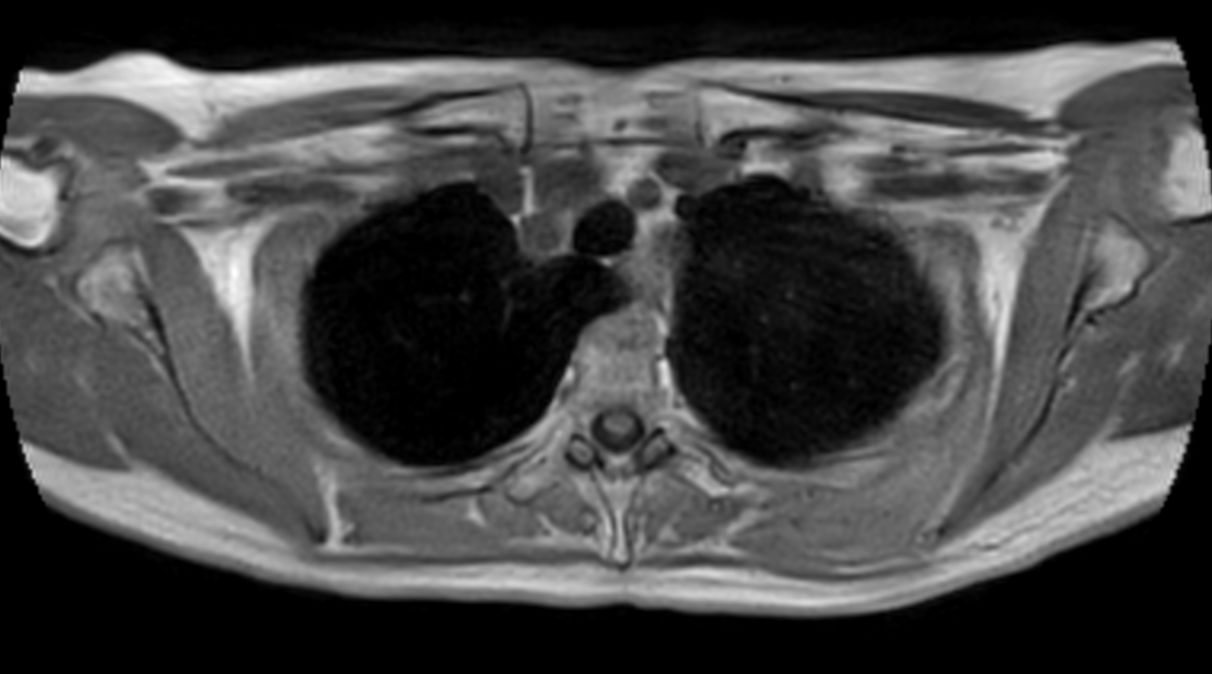

Patient with a thorax soft tissue lesion. ExamCard includes Compressed SENSE to shorten the scan time, MultiVane XD to acquire motion-free diagnostic images, 3D VANE XD helping to reduce motion artifacts during free breathing and 4D FreeBreathing to perform multi-phase contrast-enhanced MRI studies.

T2w SPIR MultiVane XD - Free Breathing